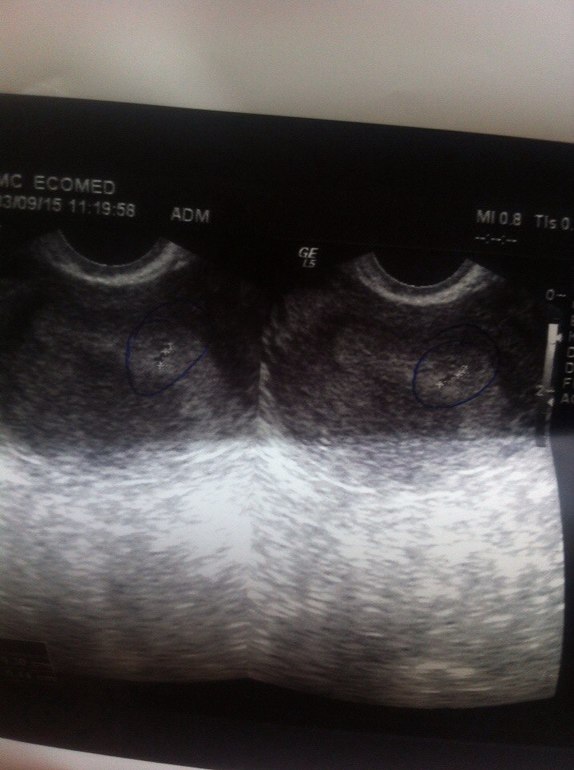

Была на узи. Задержка 1 день.

а врач не сказала вам?? у меня задержка 2 дня, тоже была на УЗИ, написали "в полости матке содержится образование похожее на плодной яйцо 0.48 см". поставили бер под вопросом, но ХГЧ 188) вопросов нет.

Это Ваш эндометрий. Если хотите посмотреть лялю на УЗИ, надо идти после 2 недель задержки, так мне говорила моя Г, вот и мы ждём с нетерпением, когда же эти две недели пройдут

если я верно понимаю, улабка это ваш эндометрий, ни че такой "улыбчивый"))